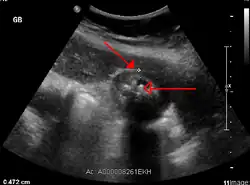

Right upper quadrant abdominal ultrasound is most commonly used to diagnose cholecystitis.[1][25][26] Ultrasound findings suggestive of acute cholecystitis include gallstones, pericholecystic fluid (fluid surrounding the gallbladder), gallbladder wall thickening (wall thickness over 3 mm),[27] dilation of the bile duct, and sonographic Murphy's sign.[13] Given its higher sensitivity, hepatic iminodiacetic acid (HIDA) scan can be used if ultrasound is not diagnostic.[13][14] CT scan may also be used if complications such as perforation or gangrene are suspected.[14]

Abdominal ultrasonography showing gallstones, wall thickening and fluid around the gall bladder

Acute cholecystitis as seen on ultrasound. The closed arrow points to gallbladder wall thickening. Open arrow points to stones in the GB